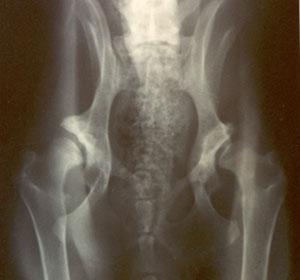

This is Jessica, CH. Dark Star's Uptown Girl, CGC, TDI, she was 26 months of age at the time of her x-ray. They look pretty good: her OFA number was: LR-47905G26F-T - she was the 47905th Labrador Retriever to receive a permanent OFA number, she received the rating of "GOOD", was 26 months of age at the time of the radiograph, is Female, and has a Tattoo. The OFA made it easier to read, decipher, and understand the permanent numbers!